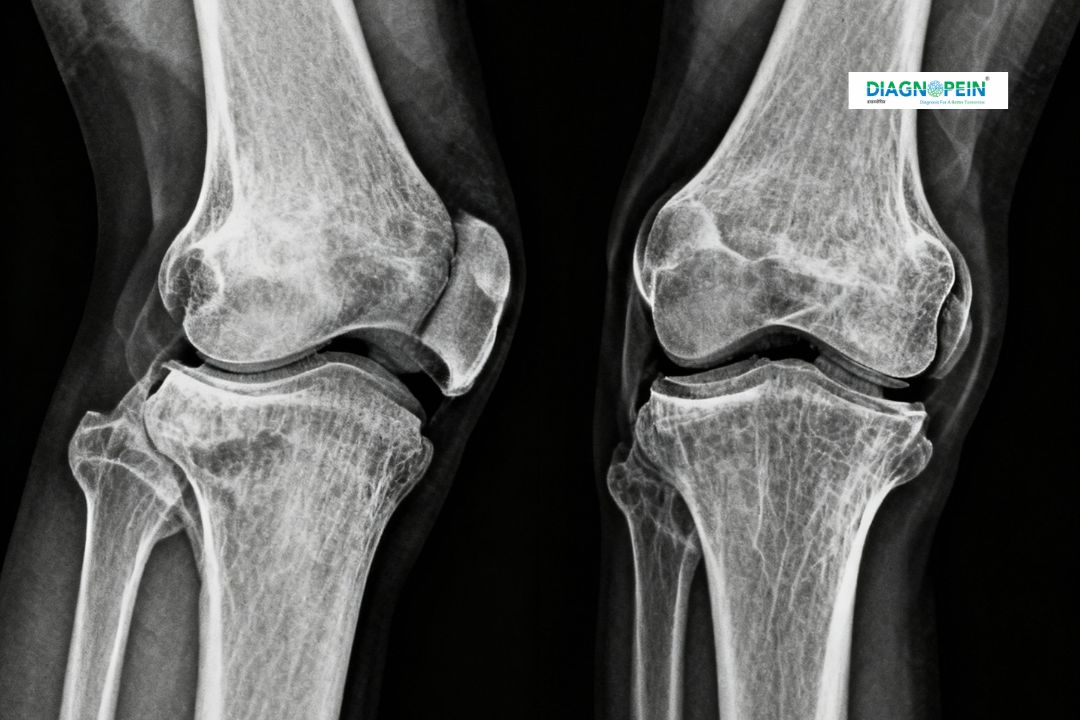

X-Ray Both Knee Merchant View is a specialized radiographic test used to evaluate the alignment, structure, and joint space of both knees under weight-bearing conditions. This imaging helps in detecting early degenerative changes, arthritis, bone deformities, and knee joint injuries. At Diagnopein, X-Ray Both Knee Merchant View in Karad is performed using advanced digital X-ray technology that provides high-quality images with minimal radiation exposure. The test is quick, safe, and non-invasive, making it an essential diagnostic procedure for orthopedic evaluation.

This test is prescribed by doctors when patients experience persistent knee pain, stiffness, or reduced mobility. It helps visualize how both knees function and align when standing. The Merchant view particularly assesses the patellofemoral joint, which plays a critical role in smooth knee movement.

The radiologist analyzes several key parameters, such as:

1. Patellofemoral joint space width

2. Knee cap alignment and shape

3. Bone surface continuity

4. Presence of spurs, fractures, or calcification

5. Bilateral comparison between knees

These findings help orthopedic specialists to develop an effective treatment plan. At Diagnopein Karad, cutting-edge technology ensures high-resolution imaging and accurate reporting to support better clinical outcomes.